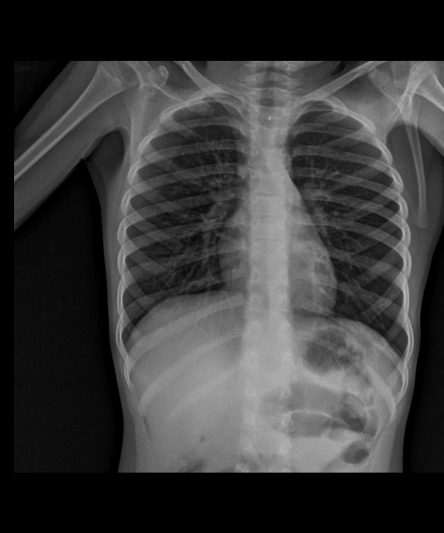

Microskan with Ultra high frequency can take the Lateral Lumbar Spine image of a 90 kg Patient with the correct image receptor